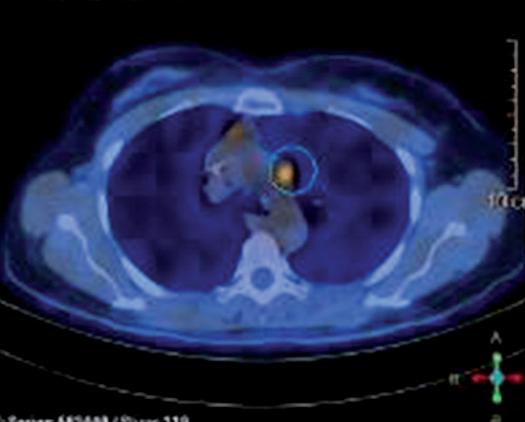

Alla RMN encefalo con mdc di approfondimento venivano evidenziate plurime lesioni ripetitive (almeno 10)

in sede sovratentoriale (diametro massimo 10x12 mm in sede temporale destra) circondate da alone di edema. Ulteriore lesione sospetta in sede sottotentoriale vermiana paramediana destra (2,5x2,5 mm circa) (figura 1a e 1b).

Per la progressione encefalica e linfonodale a livello del collo si è optato per trattamento radiante panencefalico e a passaggio a terapia di seconda linea con T-DXd5. Dal 23 ottobre al 6 novembre 2023 la paziente è stata pertanto sottoposta a radioterapia su encefalo in toto (30Gy tot 3Gy/frazione in 10 frazioni). Al termine della radioterapia, nel dicembre 2023, la paziente ha avviato 1° ciclo di T-DXd (5,4 mg/kg q21).

Alla TC total body con mdc di ristadiazione di febbraio 2024 (dopo 5 cicli di terapia con T-DXd) si è evidenziato un quadro di remissione completa in tutte le sedi di malattia interessate: encefalica, mammaria, epatica e linfonodale.

Figura 1a e 1b. Evoluzione della neoplasia mammaria primitiva dalla diagnosi in aprile 2023 alla risposta dopo 7 cicli di T-DXd in aprile 2024.

Figura 2a e 2b. Risposta intracranica completa dopo RT e T-DXd.

2a

2b